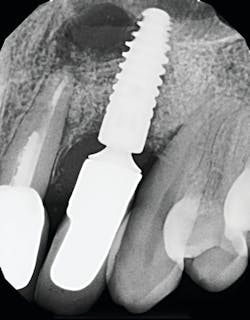

Once again, the literature is replete with case reports and case series describing soft- and hard-tissue loss due to excess dental cement left at the time of implant crown insertion.8 In one study, 90% of the implant crowns inserted with cement exhibiting inflammation and bleeding upon probing were due to cement in the peri-implant sulcus.9 Cement acts as a nidus for bacteria and induces a rapid hard-tissue loss around the dental implant fixture (figures 2 and 3).

Detecting excess cement can usually be done with a radiograph if the cement is located in the interproximal region and is radiopaque (figure 4).